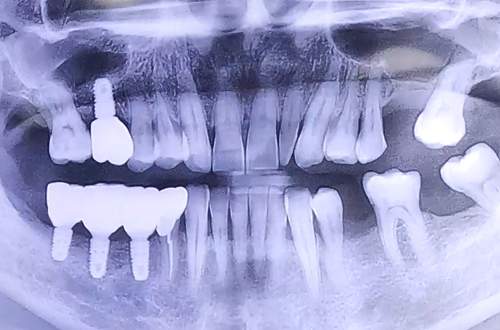

BEFORE

양쪽 모두 어금니 상태가 좋지 못하여 음식을 제대로 드시지 못하는 상태의 환자분 진료 내용입니다.